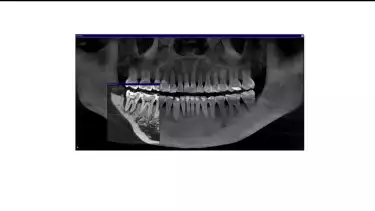

Setelah melihat hasil rontgen, drg. Devya menjelaskan, “Sebelah kanan kondisinya masih lebih baik, jadi itu yang akan kita prioritaskan dulu.” Tulang di sekitar gigi kanan Marcella masih cukup kuat untuk mendukung gigi, membuat kondisinya lebih stabil dibandingkan gigi kiri. Oleh karena itu, perawatan difokuskan terlebih dahulu pada gigi kanan untuk memaksimalkan peluang pemulihan sebelum beralih ke gigi lainnya.